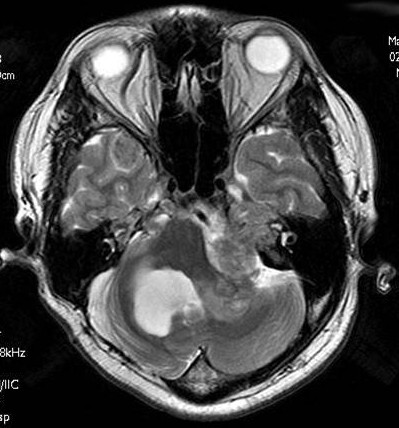

類表皮腫(epidermoid)  T1WI_axi_1  T2WI_axi_1  DWI_1